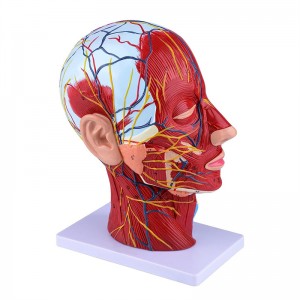

| Features | The model shows the local morphology of the inner and outer sides of the Median sagittal section of the head and neck, as well as the structures of blood vessels and nerves, and there are 84 parts indicating signs in total. |

【Superficial Neurovascular Muscle Model】Highly detailed, numbers marked, detachable ear, deepen the understanding of the superficial muscles, vessels, nerves and the internal structures of the head & neck. Red-artery, blue-vein, yellow-nerve.

【Features】It shows the superficial muscles of the exposed face; the superficial blood vessels & nerves of the face & scalp; the inner structures of parotid gland & upper respiratory tract; the sagittal cross-section structure of the cervical spine.

This model shows details of the right head neck and mid sagittal section of the human. including the superficial

muscles of the exposed face; the superficial blood vessels and nerves of the face and scalp; the inner structures

of parotid gland and upper respiratory tract; the sagittal cross-section structure of the cervical spine.

The model showed the local morphology of the medial and lateral sagittal sections of the head and neck and its vascular and nerve structures, with a total of 100 site indicators.

This model is a natural large head and neck superficial neurovascular muscle model, 1 component, showing the details of the human right head and neck and median sagittal section, including the exposed superficial muscles of the face, superficial vessels of the face and scalp, nerves and the medial structure of the parotid gland and upper respiratory tract, and the sagittal section structure of the cervical spine